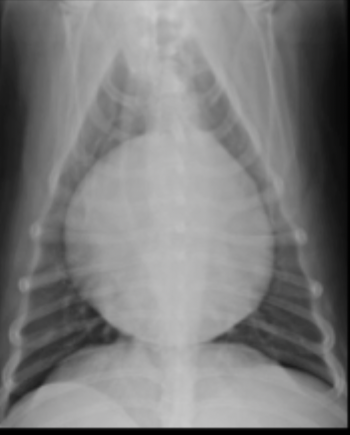

What can be seen in this canine radiograph?

pericardial effusion

What are abdominal manifestations of pericardial effusion?

dilated CVC

hepato-splenomegaly

ascites

What border description of the heart can be associated with pericardial effusion?

curved caudal dorsal border

What are causes of pericardial effusion?

idiopathic (golden retrievers)

neoplastic (right atrial tumors or chemodectomas)

hemorrhage